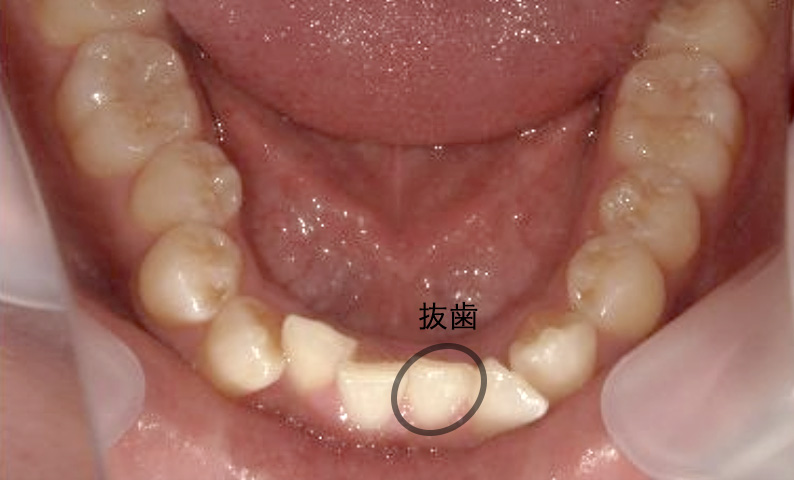

症例_004 下顎だけの部分矯正

治療期間:7ヶ月金額:24万円+税男性前歯のガタガタ下の前歯だけ

| Before | After |